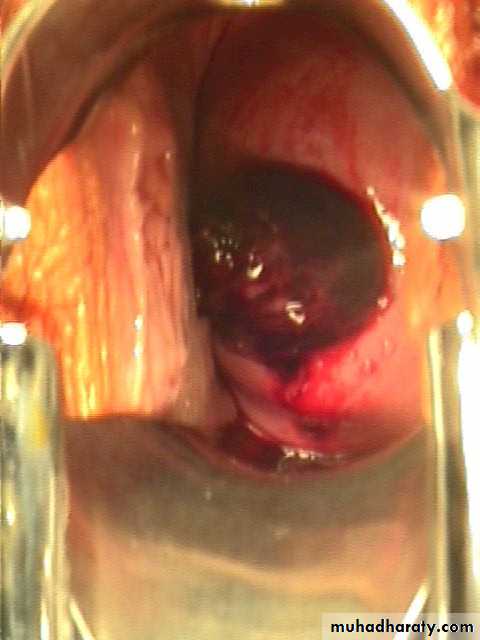

Incomplete abortion with products of conception passing through the dilated cervical os